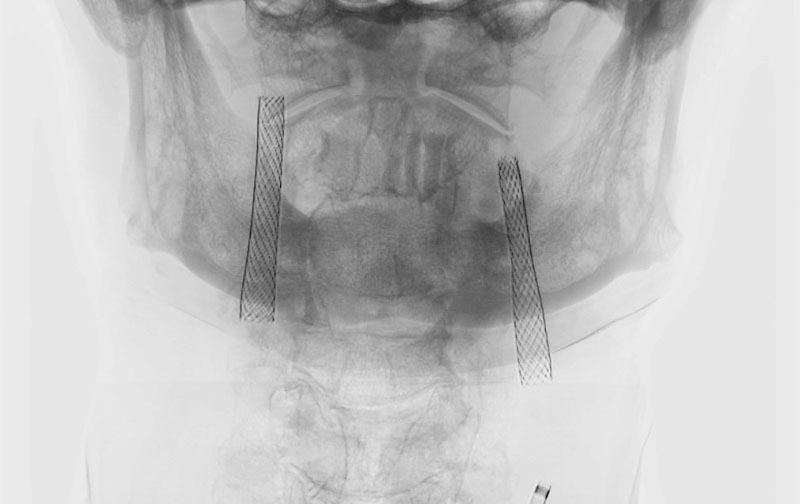

症例 '22年3月

No.

1201

'22年3月4日

右内頚動脈狭窄症

80代

大阪府の病院

手術写真